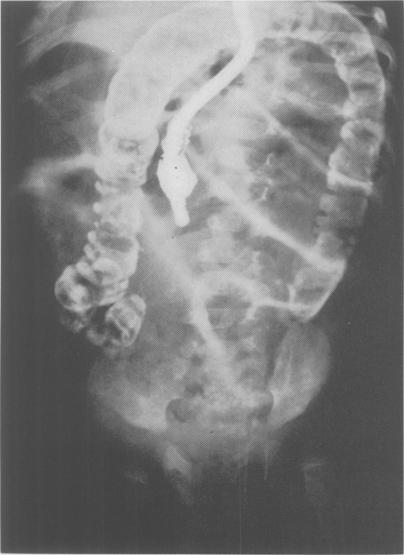

Intestinal obstruction in the newborn caused by agenesis of the myenteric plexus of the entire colon; case report.

Ann Surg. 1956 Dec;144(6):1062-6. doi: 10.1097/00000658-195612000-00019.